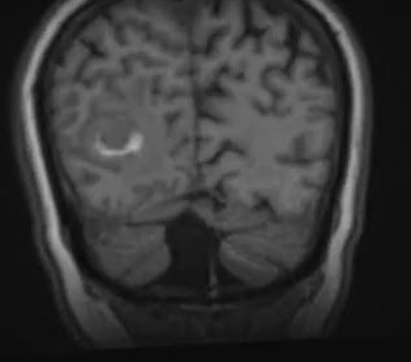

CAZ nr 95: Leziuni intracerebrale de tip hemoragic în evoluţie – probabil amiloidoză cerebrală.

Discuţie caz nr 95: prima examinare la o pacienta cu cefalee, amețeli – suspiciunea a fost de determinări secundare cerebrale probabil melanom iar pacienta a completat cu PET-CT cu protocol de melanom care a fost negativ. Două luni mai târziu pacienta repetă examinarea IRM înaintea unei puncții intracerebrale pentru diagnostic și s-a evidențiat reducere marcată a volumului lezional. Iar ultima investigație a fost realizată pentru simptomatologie neurologică nou apărută. Comparând cele trei examinări, se remarcă prezența de multiple leziuni infra și supratentorial cu aspect de sângerare care involuează în timp iar suspiciunea este de amiloidoză izolată intracerebrală.